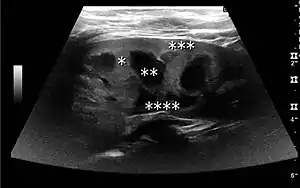

Complex cysts can have membranes dividing the fluid-filled center with internal echoes, calcifications or irregular thickened walls. The complex cyst can be further evaluated with Doppler US, and for Bosniak classification and follow-up of complex cysts, either contrast-enhanced ultrasound (CEUS) or contrast CT is used (Figure 6). The Bosniak classification is divided into four groups going from I, corresponding to a simple cyst, to IV, corresponding to a cyst with solid parts and an 85–100% risk of malignancy.[1] In polycystic kidney disease, multiple cysts of varying size in close contact with each other are seen filling virtually the entire renal region. In advanced stages of this disease, the kidneys are enlarged with a lack of corticomedullary differentiation (Figure 7).[1]

Figure 6. Complex cyst with thickened walls and membranes in the lower pole of an adult kidney. Measurements of kidney length and the complex cyst on the US image are illustrated by '+' and dashed lines.[1]